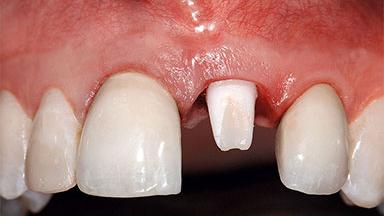

A healthy 37-year-old female patient was referred for a consultation on the replacement of missing tooth 21 with an implant-supported restoration. She stated that several years previously the tooth had been traumatically avulsed following a motor vehicle accident. The tooth was replaced with a three-unit fixed partial denture (FPD) immediately afterwards. Over time, she became disillusioned with the FPD and looked for a different option, including orthodontic therapy. She presented still in her orthodontic appliances, with the pontic sectioned free from the FPD but attached to the archwire. Her orthodontist felt that orthodontic treatment had been successfully completed, but nevertheless referred her before removing the appliances in case adjustments were necessary.